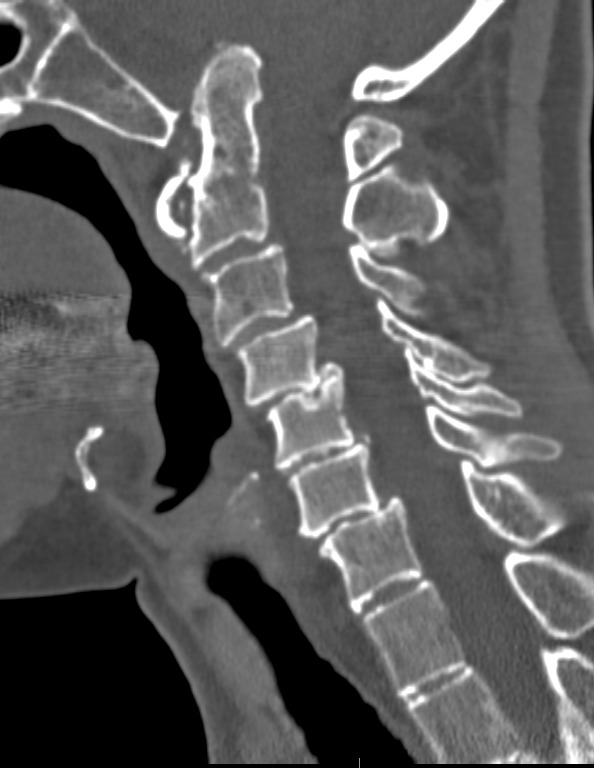

1. CT of CVJ. Left: coronal CT shows severely upslanting and elevated left occipital condyle–C1 joint (arrows). C4 is a hemi-vertebra. Right: sagittal CT shows invagination of the opisthion (Op) (basilar invagination). The posterior arch of C1 is assimilated into the posterior rim of the foramen magnum. Note slightly high-riding odontoid but absence of platybasia, short clivus or retroflexed dens.